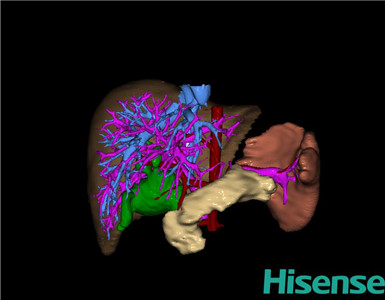

CT结果输入海信CAS系统后行3D重建及手术规划后,于2016-8-23全麻下行“胆总管切除术”手术治疗:

术前三维重建及手术方案设计:

将0.625mm双源薄层CT资料的静脉期和动脉期Dicom格式文件导入海信CAS系统。

通过调节窗宽窗位调整CT序号,对肝实质,胆囊,下腔静脉,肿瘤,肝动脉、门静脉及肝静脉等进行三维重建;系统自动计算肝脏体积。

术前三维重建:

重建图片